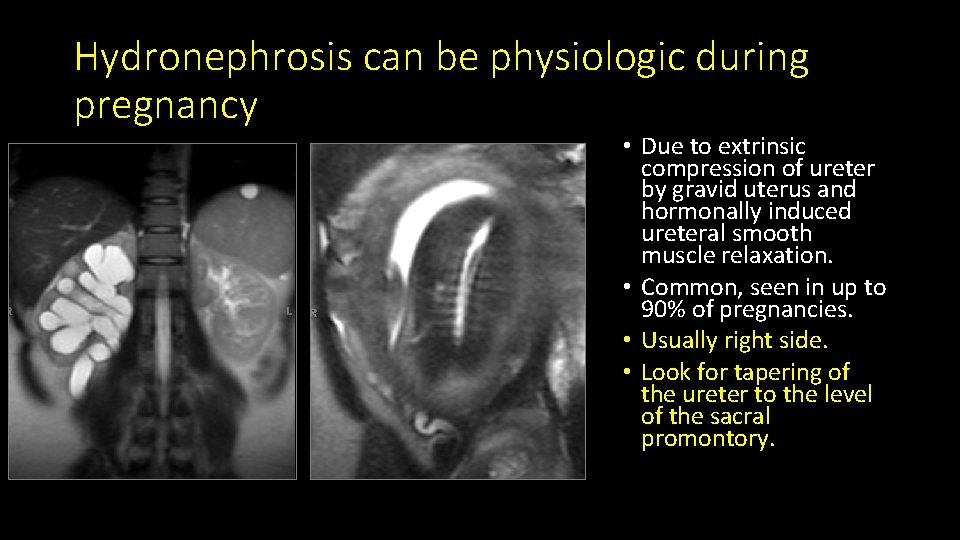

Hydronephrosis can be physiologic during pregnancy • Due to extrinsic compression of ureter by gravid uterus and hormonally induced ureteral smooth muscle relaxation. • Common, seen in up to 90% of pregnancies. • Usually right side. • Look for tapering of the ureter to the level of the sacral promontory.